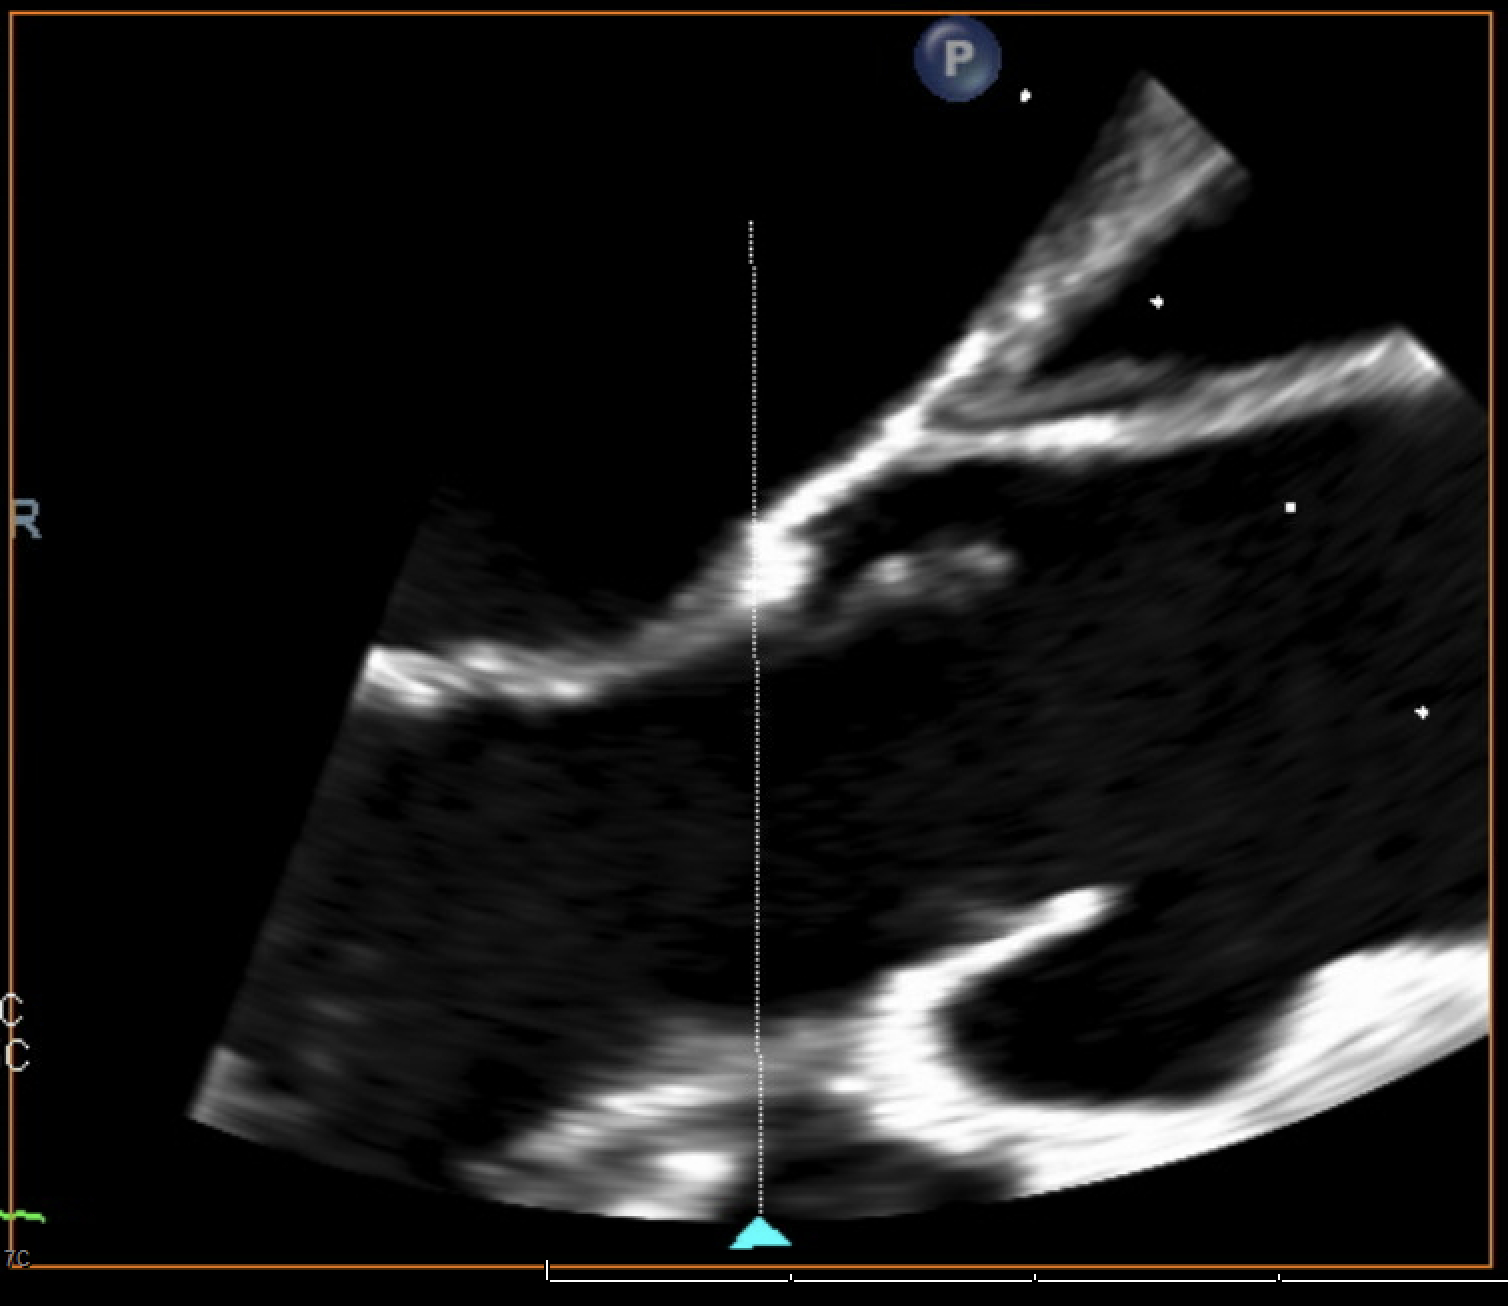

Due to persistent bacteremia and worsening hemodynamics, a repeat TEE was performed, which revealed a new, large circumferential pericardial effusion with right atrial systolic collapse, right ventricular diastolic collapse, plethoric IVC, a 1.4 × 0.8 cm highly mobile vegetation on the mitral valve subvalvular apparatus, and multiple large echogenic structures in the pericardial space concerning for vegetation. Pericardiocentesis revealed a purulent, MRSA-positive fluid, confirming purulent pericarditis. The antibiotics regimen was intensified and the patient was transferred to a higher level of care facility for cardiac surgery evaluation.